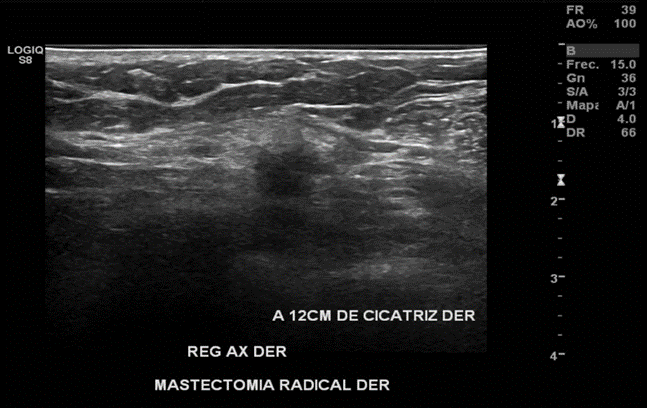

Nódulo sólido, hipoecogénico, de bordes irregulares, más alto que ancho, con sombra acústica posterior y con señal al Doppler a 12cm de cicatriz en región mamaria derecha hacia región axilar del mismo lado. Probable recidiva.

En región axilar derecha se observa imagen nodular, hipoecoica, de bordes mal definidos, de 16x12 mm.

Imagen nodular sugerente de atipia en región axilar derecha. Se sugiere estudio histológico.